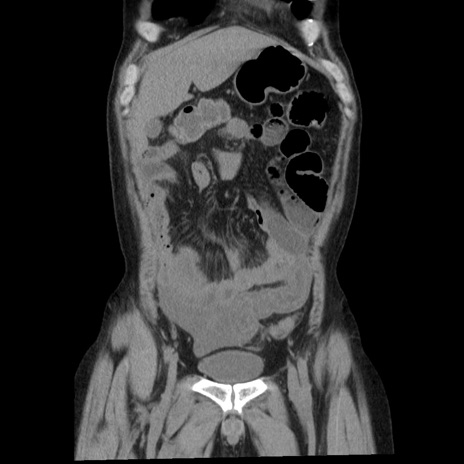

症例29(冠状断像)

【症例】40歳代男性

【現病歴】2日前から胃痛あり。徐々に周期的な激痛に変化した。本日になっても激痛があるため受診。

【身体所見】意識清明、BT 38-39℃台あり、腹部:膨満、やや硬、右下腹部に圧痛あり。

【データ】WBC 8500、CRP 23.26